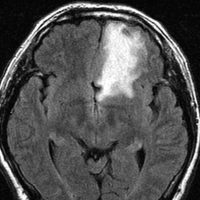

- T2強調やフレア画像では,腫瘍周囲に強い脳浮腫(脳が腫れる)があることも多いです

左は,造影剤を使ったガドリニウム増強MRIです。腫瘍が白く丸く見えます。右はフレア画像で,腫瘍の周囲の脳浮腫(脳のはれ)です。左前頭葉が,かなり強くはれています。この腫瘍は小さいのですが,脳のはれが強すぎるので手術摘出したほうがいいです。浮腫が悪化すると,てんかん発作や認知機能低下がでる可能性があります。